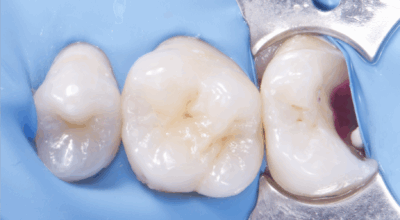

Clinical case

Direct pulp capping: 90.4% success rate